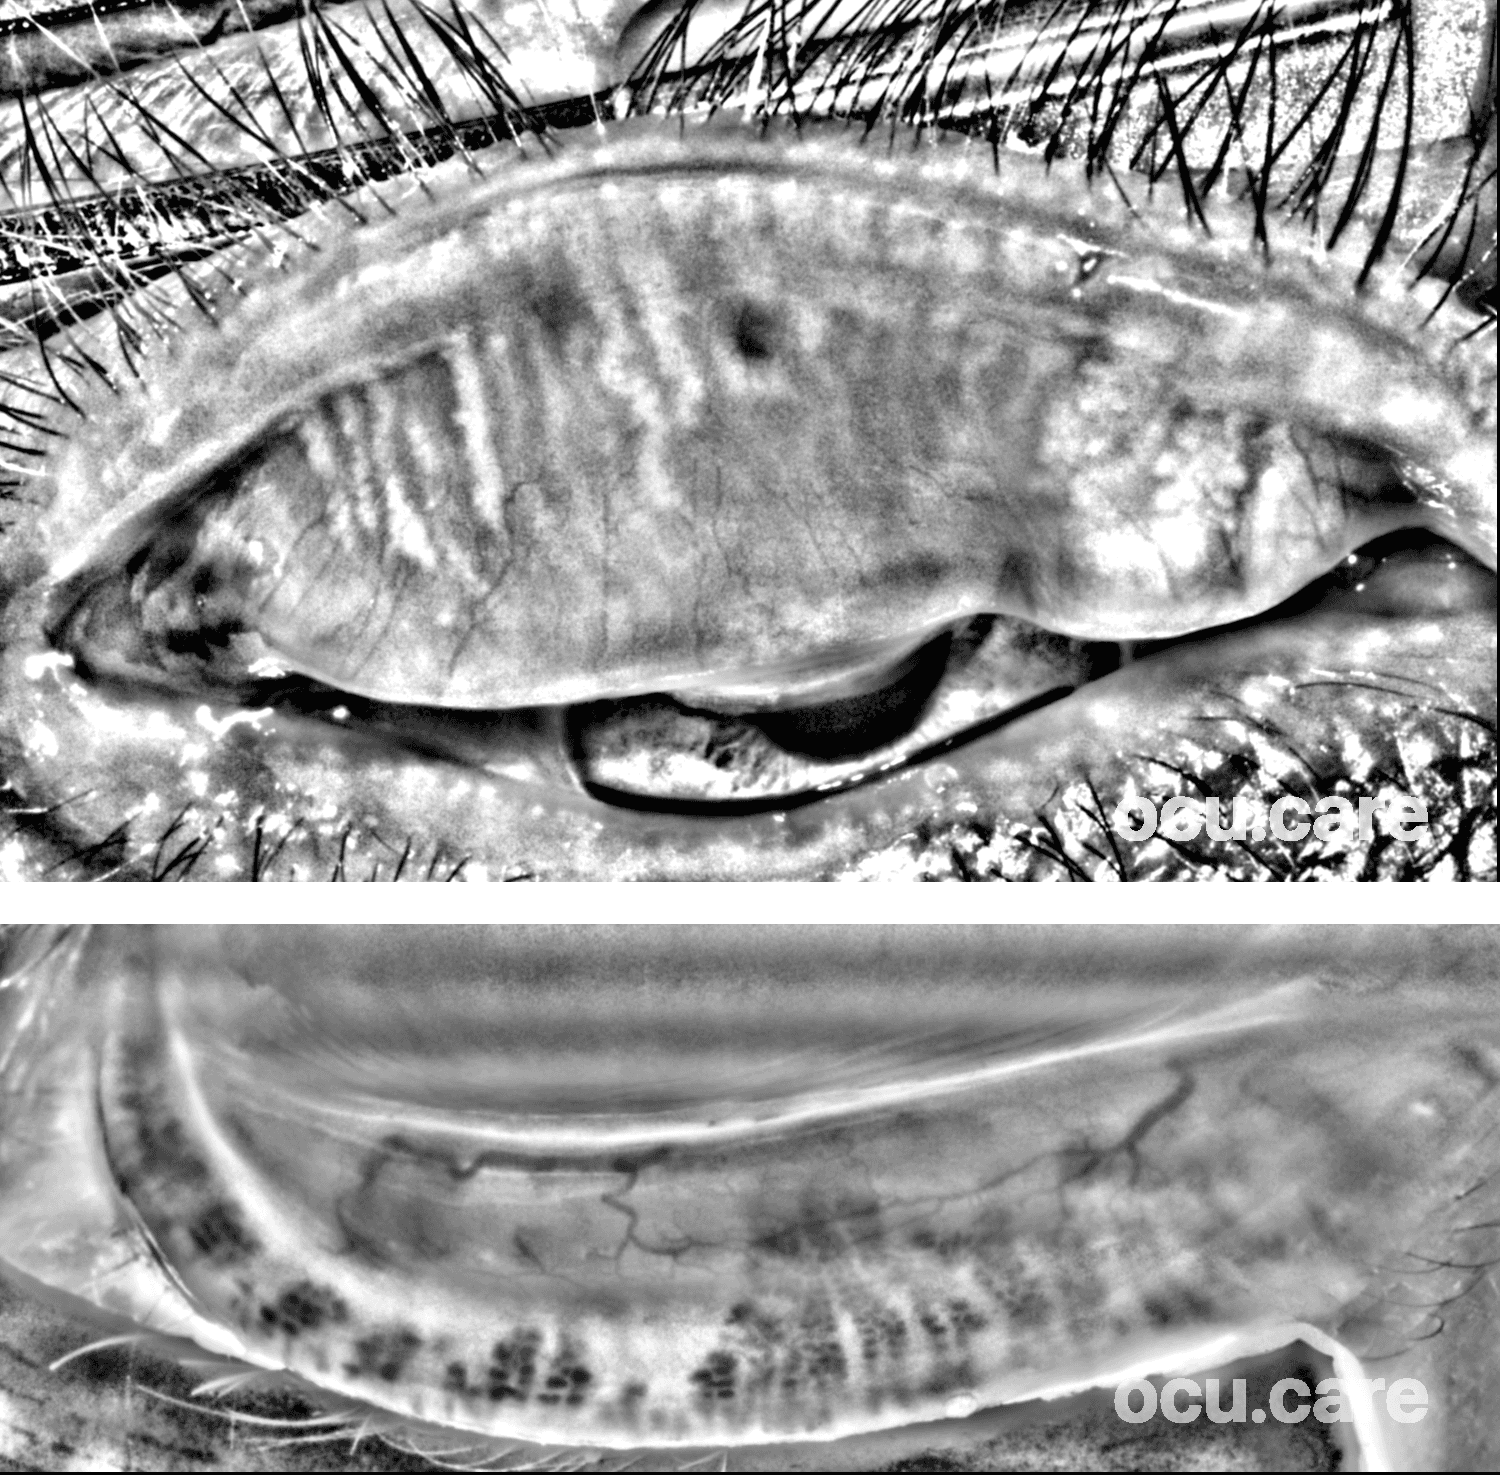

This 73-year-old gentleman has been using long-term brinzolamide preserved with benzalkonium chloride (BAK). The meibography images show several morphological changes, including gland atrophy, shortened and tortuous glands, “ghost glands”, and fluffy / abnormal gland architecture.